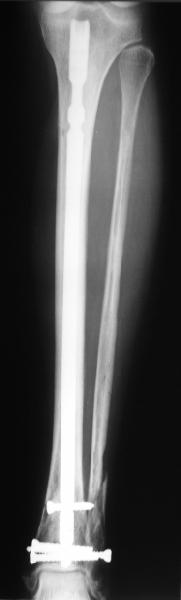

TDVC> Very interesting application, but is the final position in a

TDVC> little distal varus with some fibula distraction?

At least both the ankle mortise and tibial alignment look acceptable, don't they?

I am just trying to illustrate that prevention of 1)tibial valgus and 2)loss of reduction can be provided without fibular plating. Small changes of conventional nailing techniques allow to maintain reduction of the tibia reliably without adjunctive fibular stabilization.

In delayed cases acute length restoration performed only in the tibia may leave the fibula shortened thus change the mortise. So it is reasonable to restore length of both bones simultaneously by distractor and fix the fibula not with open reduction and plating but just by a single perQ screw. Example attached.